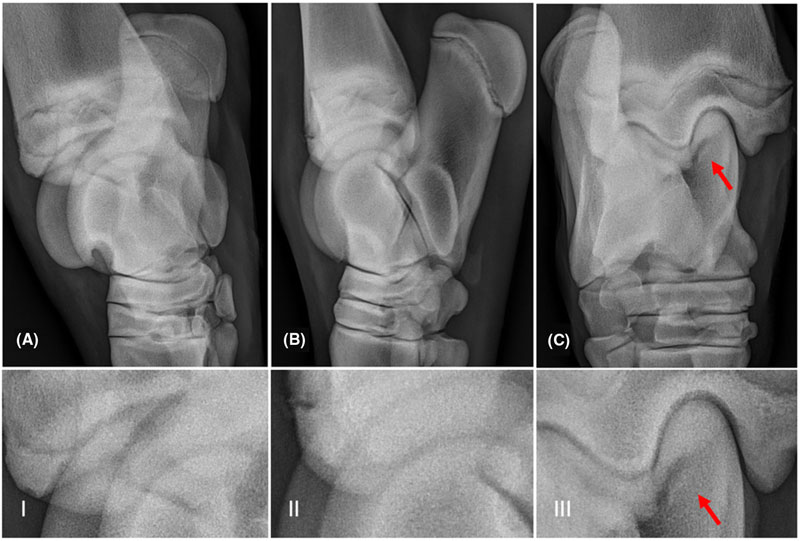

- Chụp X-quang toàn bộ xương

1. Loạn sản xương suy dinh dưỡng – Thanatophoric dysplasia (TD)

- Chi ngắn nặng, xương đùi cong như “ống nghe điện thoại”

3. Osteogenesis imperfecta type II

- Gãy xương nhiều vị trí

- Sọ mềm, dễ bị lõm khi tì đầu dò

- Xương dài cong nhiều đoạn